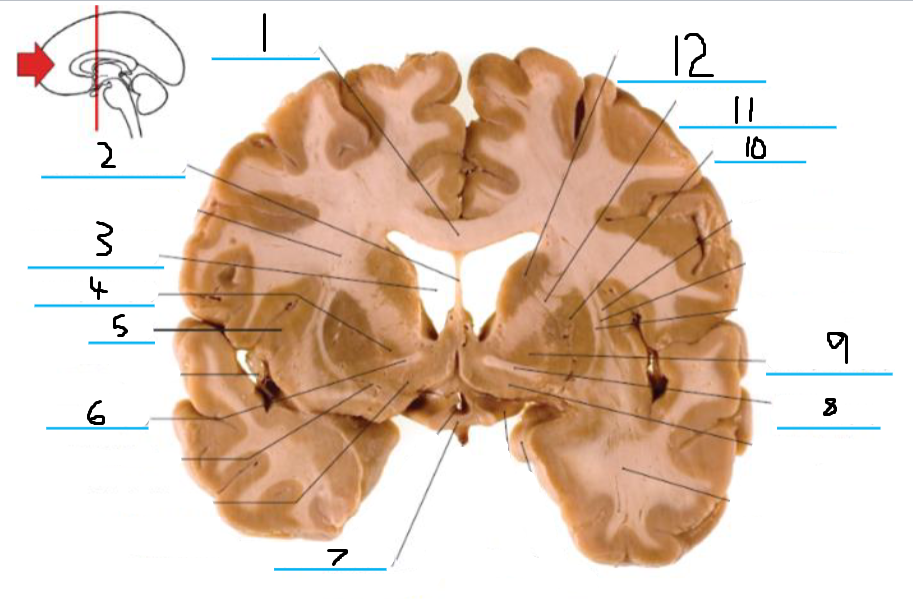

#1 is the:

Corpus Callosum

#2 is the:

Septum Pellucidum

#3 is the:

Lateral Ventricle

#4 and #9 is the:

Globus Pallidus

#5 is the:

Insula

#6 and #8 is the:

Anterior Commissure

#7 is the:

Optic Chiasm

#10 is the:

Putamen

#11 is the:

Internal Capsule

#12 is the:

Caudate